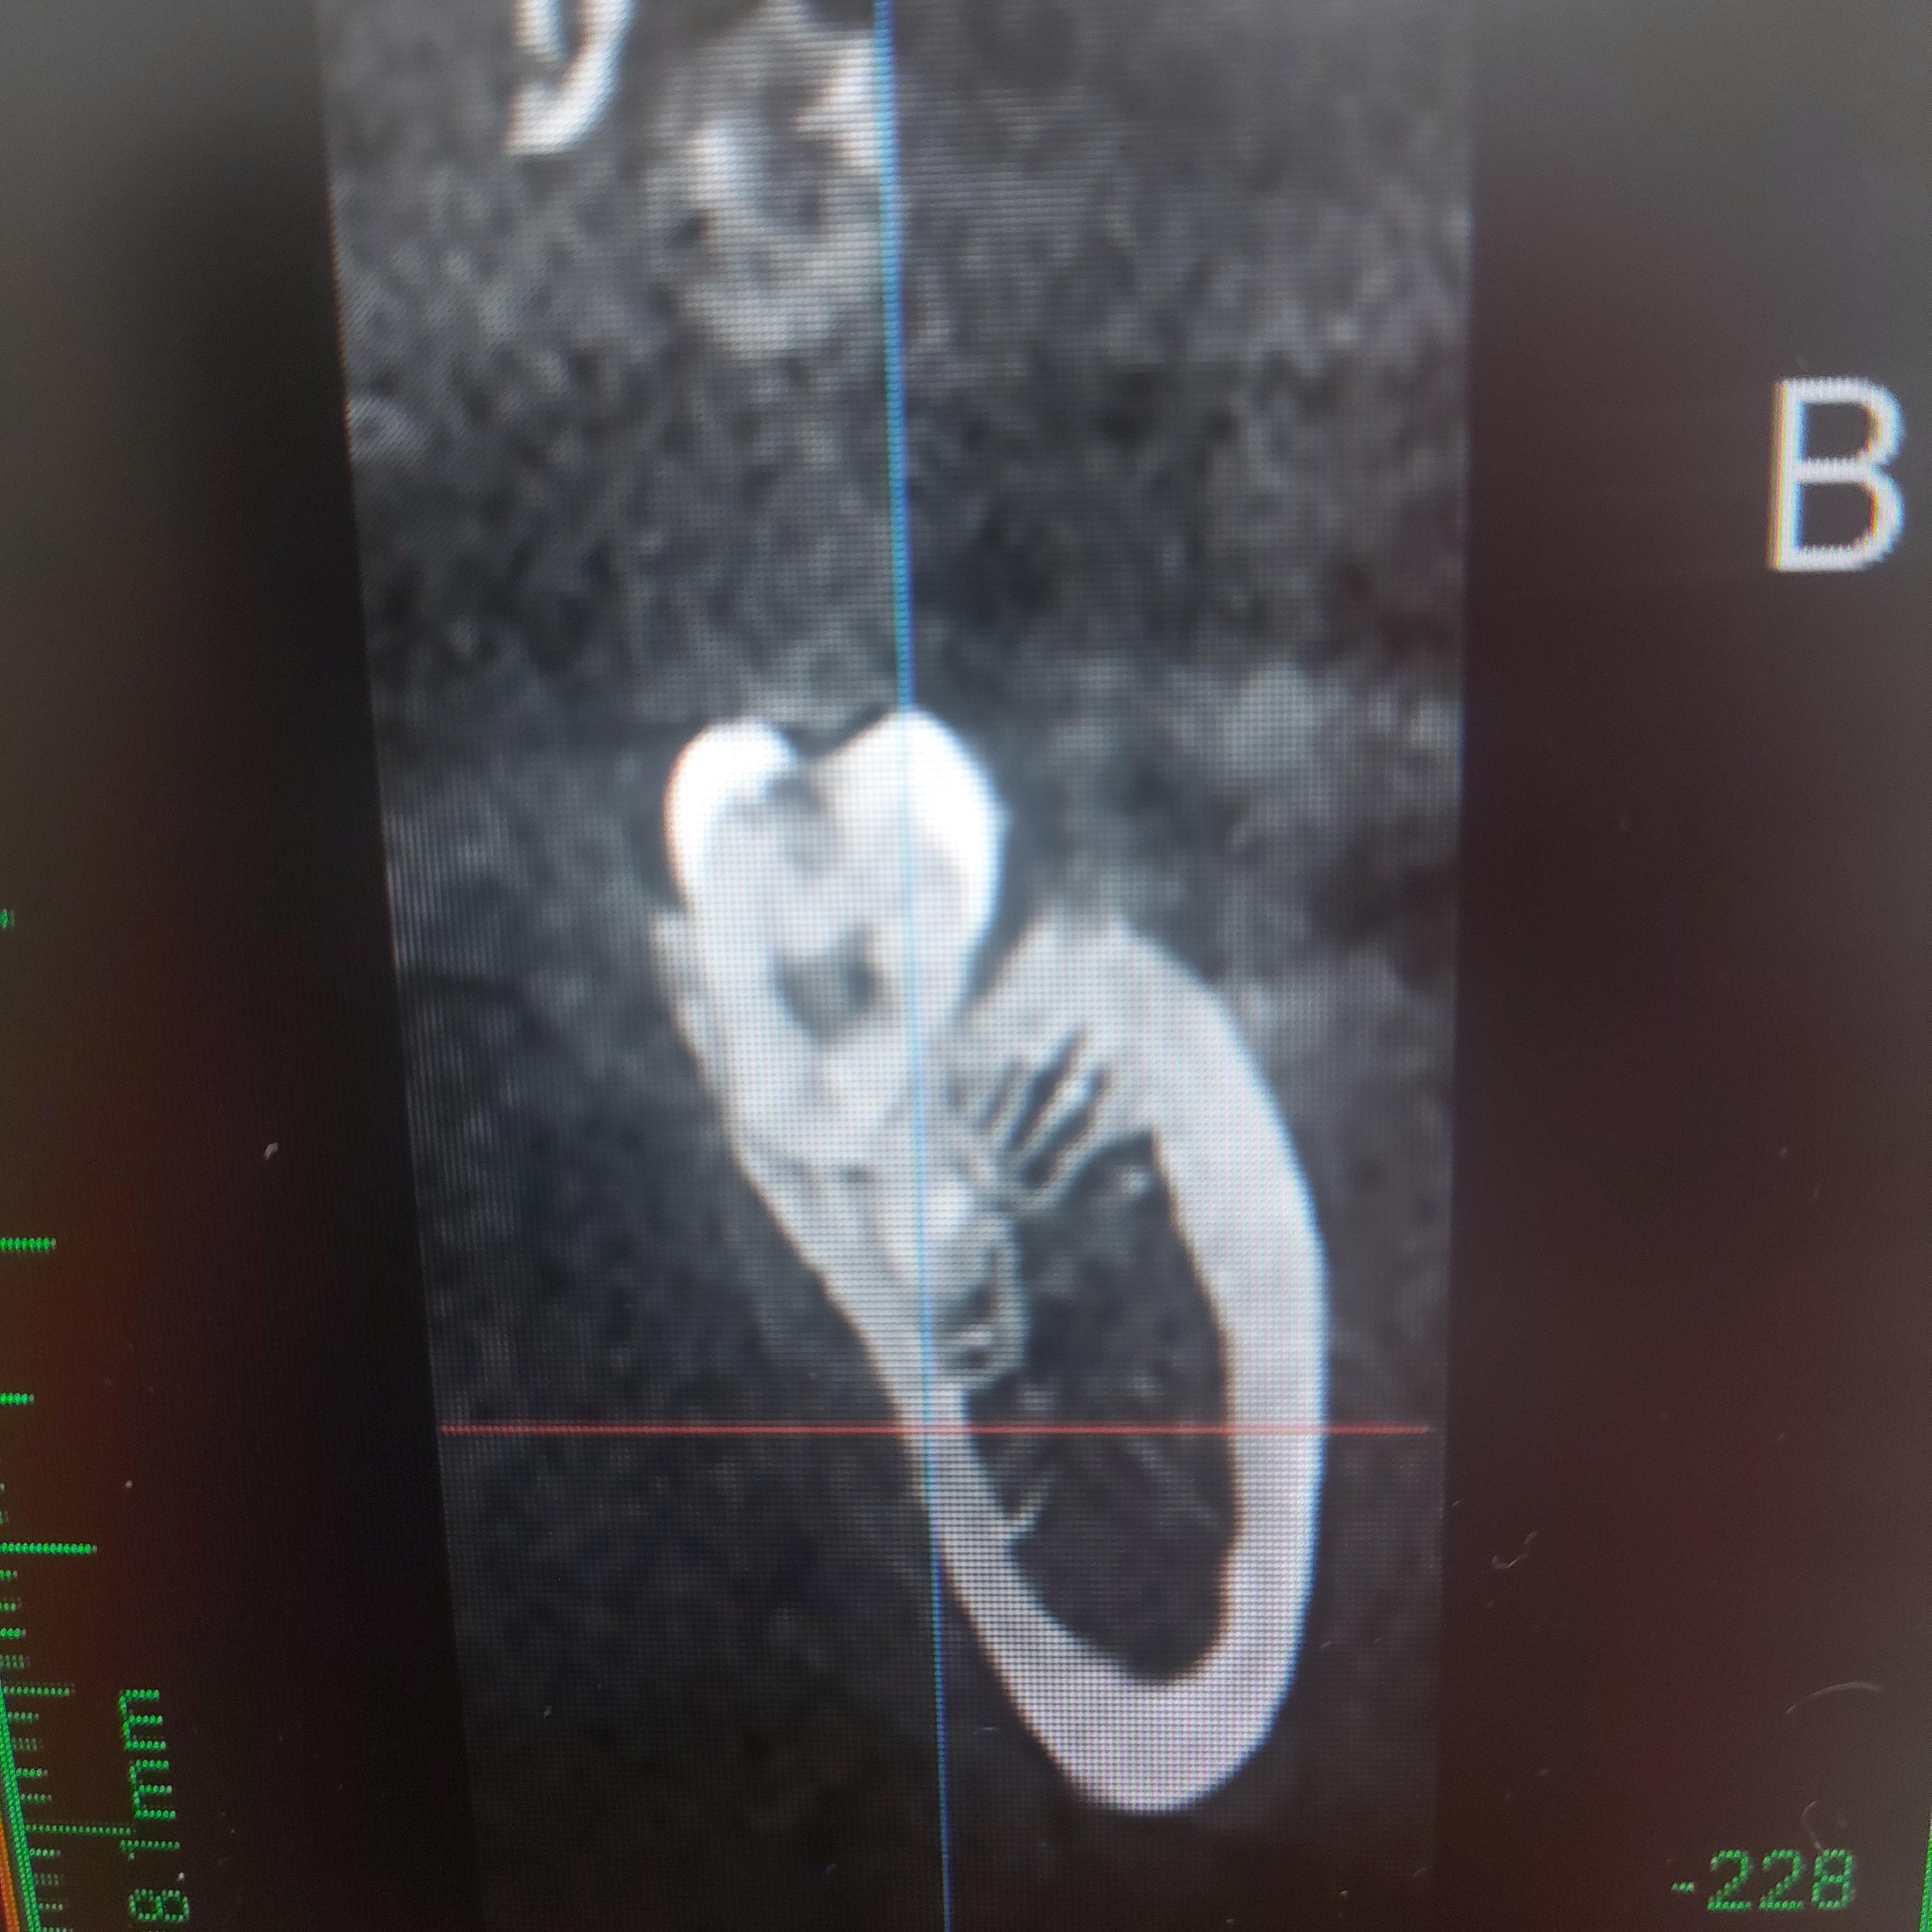

파노라마 방사선 사진상 신경관과 겹쳐 보여서 정밀 검진을 위해 CT를 찍었고 다행히 파노라마 사진상으로는 겹쳐 보이지만 실제 위치는 신경관보다 안쪽에 있다는 걸 확인 할수 있었습니다.

이번 환자분을 진료 하면서 느낀점은 파노라마 사진은 이차원적인 이미지라 옜날 지식이었다면 신경관과 겹쳐 보이고 여러가지 정황상 신경관 침입이 예상된다고 말씀드리고 대학병원으로 의뢰 하였겠지만 CT상으로 확실히 근접하고는 있지만 침범하지 않았다는 것을 확신할 수 있었습니다.